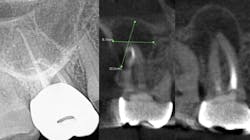

The periapical abscess that originates in the dental pulp is most often a secondary effect of dental caries. A periodontal abscess is an infection located contiguous to the periodontal pocket and may result in destruction of the periodontal ligament and alveolar bone. A periodontal abscess, the third most frequent dental emergency, has two ideologies: periodontitis related and nonperiodontitis related. Abscesses of periodontitis usually appear as an exacerbation of untreated periodontal disease or perhaps during periodontal treatment. Abscesses of nonperiodontitis-related origin frequently develop after the impaction of foreign objects, such as a piece of dental floss or abnormalities in the root enamel. A pericoronal abscess is associated with the crown of a partially erupted tooth. Like a gingival abscess, there may have been a retention of microbial plaque, food impaction, or trauma. The endo-periodontal lesions involve both the pulp and periodontal tissues, are relatively rare in clinical practice, and are one of the most challenging problems clinicians face (figure 1).

While I am not an expert, I do know that a bacterial infection inside or outside the mouth isn’t stellar for the entire body. In more than 30 years of clinical care, I can’t count the number of times I’ve seen a radiolucent area on a radiograph, when asymptomatic the treatment was nothing. There were other cases where the patient was in pain, given an antibiotic, and sent on their way. They didn’t have a follow-up appointment to treat the infection, perhaps because they couldn’t afford it or didn’t want treatment. I’m assigning no blame here, but simply stressing that we need to continue to educate our patients. Pathogens circulate and sometimes require the body’s immune system to be on overdrive, and many people’s health can’t afford to have an overactive immune system. Technology is expanding and dentistry can now utilize cone beam imaging to find abscesses that don’t present on a 2D radiograph. We can help our patients become healthier. But a silent abscess is an abscess. My friends in a Nashville dental practice recently had a case where the periapical radiograph looked completely fine, yet when a cone beam was done, an abscess showed up louder than Loretta Lynn at the Grand Ole Opry. We should be stewards of new knowledge, new technology, and be open to the expanding world of science.